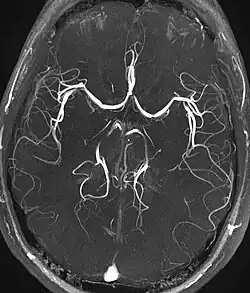

Magnetic resonance angiography (MRA) and venography Time-of-flight TOF Blood entering the imaged area is not yet magnetically saturated, giving it a much higher signal when using short echo time and flow compensation. Detection of aneurysm, stenosis, or dissection[31]

Phase-contrast magnetic resonance imaging PC-MRA Two gradients with equal magnitude, but opposite direction, are used to encode a phase shift, which is proportional to the velocity of spins.[32] Detection of aneurysm, stenosis, or dissection (pictured).[31]

Magnetic resonance angiography

Time-of-flight MRA at the level of the Circle of Willis.

Magnetic resonance angiography (MRA) is a group of techniques based to image blood vessels. Magnetic resonance angiography is used to generate images of arteries (and less commonly veins) in order to evaluate them for stenosis (abnormal narrowing), occlusions, aneurysms (vessel wall dilatations, at risk of rupture) or other abnormalities. MRA is often used to evaluate the arteries of the neck and brain, the thoracic and abdominal aorta, the renal arteries, and the legs (the latter exam is often referred to as a "run-off").